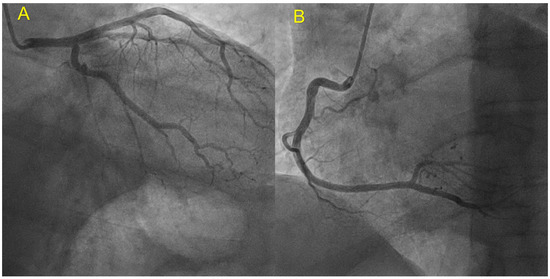

| Echocardiography | Hypokinetic non-dilated cardiomyopathy LVEF = 42% Mild mitral regurgitation IAS aneurysm | Hypokinetic non-dilated cardiomyopathy LVEF = 34% Mild mitral regurgitation IAS aneurysm | Left ventricular concentric hypertrophy LVEF = 54% |

| Cardiac magnetic resonance imaging | Hypokinetic non-dilated cardiomyopathy Left ventricular non-compaction LVEF = 50% | Hypokinetic non-dilated cardiomyopathy Regional sub-epicardial fibrosis LVEF = 41% | Not carried out |

| Coronary angiography | Normal | Normal | Not carried out |